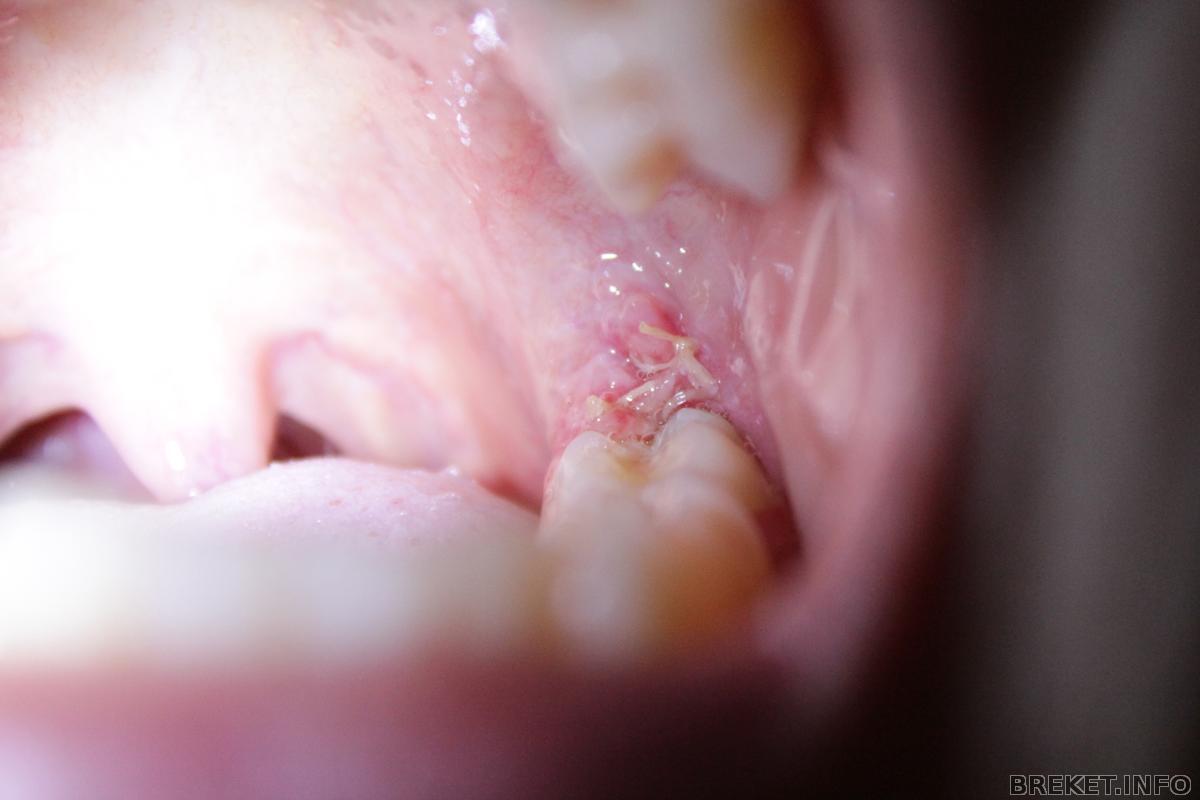

начинает зашивать... и говорит мне: "всё, с зубами мудрости покончено) вырастешь, скажи своему жениху что в детстве зубастая была. хорошо что хирург вовремя удалил, а то покусаала бы))" я сижу, с открытым ртом, смеюсь ![]()

марина борисовна, vikatosha, у меня восьмёрки в горизонтальном положении ![]()